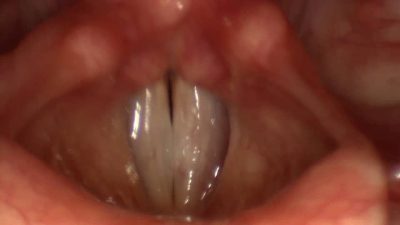

تارهای صوتی (Vocal Cords) دو چین عضلانی انعطاف پذیر هستند که درون حنجره (Larynx) قرار دارند. حنجره در قسمت جلویی گردن، دقیقاً در بالای نای و پشت برجستگی حنجره ای یا همان سیب آدم واقع شده است. این تارها بخشی حیاتی از سیستم تولید صوت در بدن انسان به شمار می آیند. فهم دقیق اینکه عملکرد تارهای صوتی گلو چیست و صدا چگونه تولید می شود، مستلزم شناخت ساختار، مکانیزم و عوامل فیزیولوژیکی درگیر در این فرآیند است.

زمانی که فرد نفس می کشد، تارهای صوتی باز می مانند تا هوا آزادانه از ریه ها به نای و در نهایت به بیرون منتقل شود. اما زمانی که فرد قصد صحبت کردن یا آواز خواندن دارد، تارهای صوتی به یکدیگر نزدیک می شوند. هوای بازدمی که از ریه ها خارج می شود، با فشار به این تارها برخورد کرده و باعث ارتعاش آن ها می شود. این ارتعاش ها همان چیزی هستند که منجر به تولید صدا می گردند. فرکانس این ارتعاشات، که به تعداد لرزش ها در هر ثانیه بستگی دارد، تعیین کننده ی زیر یا بم بودن صداست.

تارهای صوتی از سه لایه اصلی تشکیل شده اند.

لایه بیرونی یا اپیتلیوم، سطح صاف و لغزنده ای است که تماس با هوای عبوری را تنظیم می کند. لایه میانی، شامل ساختارهای الاستیک و ژله مانند است که خاصیت ارتجاعی دارند. درونی ترین بخش نیز عضله ویسکولاریس است که با تغییر طول و کشش تارها، تن صدا را تغییر می دهد. تمام این لایه ها با همکاری یکدیگر، باعث تولید صدای طبیعی، پیوسته و هماهنگ می شوند.